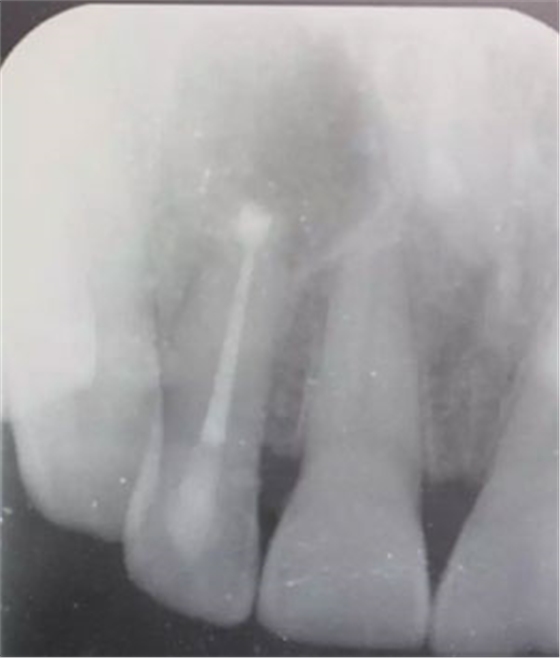

圖1.患者在根管術(shù)前的根尖片影像檢查:12有開髓孔,根尖有橢圓形陰影。

患者、張xx、前牙唇側(cè)牙齦反復(fù)溢膿數(shù)年?,F(xiàn)病史:患者數(shù)年前、無誘因發(fā)現(xiàn)前牙牙齦腫痛溢膿,曾在當?shù)鼐驮\,治療經(jīng)過不詳,治療效果不佳,唇側(cè)溢膿現(xiàn)象為消除,遂來我院就診。??茩z查:21舌側(cè)有開髓孔、根管開放,牙冠成灰褐色。唇側(cè)粘膜有一膿瘺。捫診溢膿。12無松動。x光檢查:12根尖區(qū)橢圓形陰影,界限清楚。診斷:12根尖周炎伴發(fā)根尖囊腫。治療:12行根管治療。一個月后。唇側(cè)膿瘺未消失。建議根管外科手術(shù),患者同意手術(shù)。簽手術(shù)知情同意書。